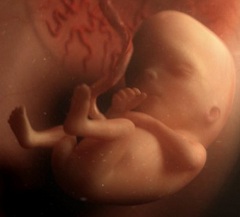

Размер плода на 13 неделе беременности - 7 смНа 13 неделе беременности плоду исполняется 11 недель с момента зачатия. Ему уже полных 3 календарных месяца, также это начало 4-го лунного месяца.

Размер плода на 13 неделе беременности достигает 7 см, а весит он около 23 г. Тело его постепенно вытягивается в длину, и соотношение голова/туловище постепенно уменьшается, поэтому голова выглядит уже не такой большой.

Движения плода на 13 неделе беременности активные и не такие хаотичные, как прежде. Это можно заметить на УЗИ в 13 недель беременности. Малыш ощупывает части своего тела, пуповину, строит гримасы и потягивается. Он еще не видит – глазки прикрыты веками, но уже реагирует на свет. Мимическая мускулатура пока сформирована таким образом, что малыш только хмурится и «сердится». Мышцы, формирующие непроизвольную улыбку, еще недоразвиты.

В коже плода образовались тактильные рецепторы, благодаря чему он ощущает прикосновения и давление. Будущий ребенок с 13 недель беременности реагирует на смену положения матери, и сам по несколько раз в день меняет свою позу в матке. Сформировались потовые железы в коже, а на голове – первые волосы.

На этом сроке сердце плода уже заключено внутри грудной клетки, спереди защищено хрящевой основой грудины, появились зачатки ребер. В скором времени малыш будет пытаться совершать тренировочные дыхательные движения.